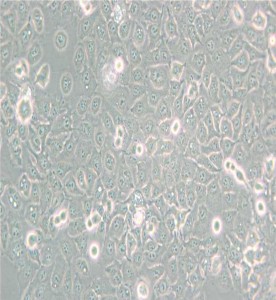

KYSE-150人食管鱗癌細胞

細胞形態 :上皮細胞樣

生長特性 :貼壁細胞

E stablished from the poorlydifferen tiated esophagealsquam ouscellcarcinom a resected from upper (cervical) esophagusofa 49-year-old Japanesew om an afterreceiving radio therap y(tum orwasin vading contigu o u s stru ctu res);d escribed ascarryingam plified oncogenes,c-erb-B (8x)and cyclin D 1(4x)and producingtum orsin nudemice.

倍增時間:13.7hours(PubMed = 1728357); 23 hours(PubM ed = 25984343);<25hours,lessw hen serum am ountisincreased (D SM Z)

供體年齡 :女;49歲

組織來源 :食管

細胞類型 :腫瘤細胞

腫瘤類型 :食管癌細胞

致瘤性 :Yes,in nudemice